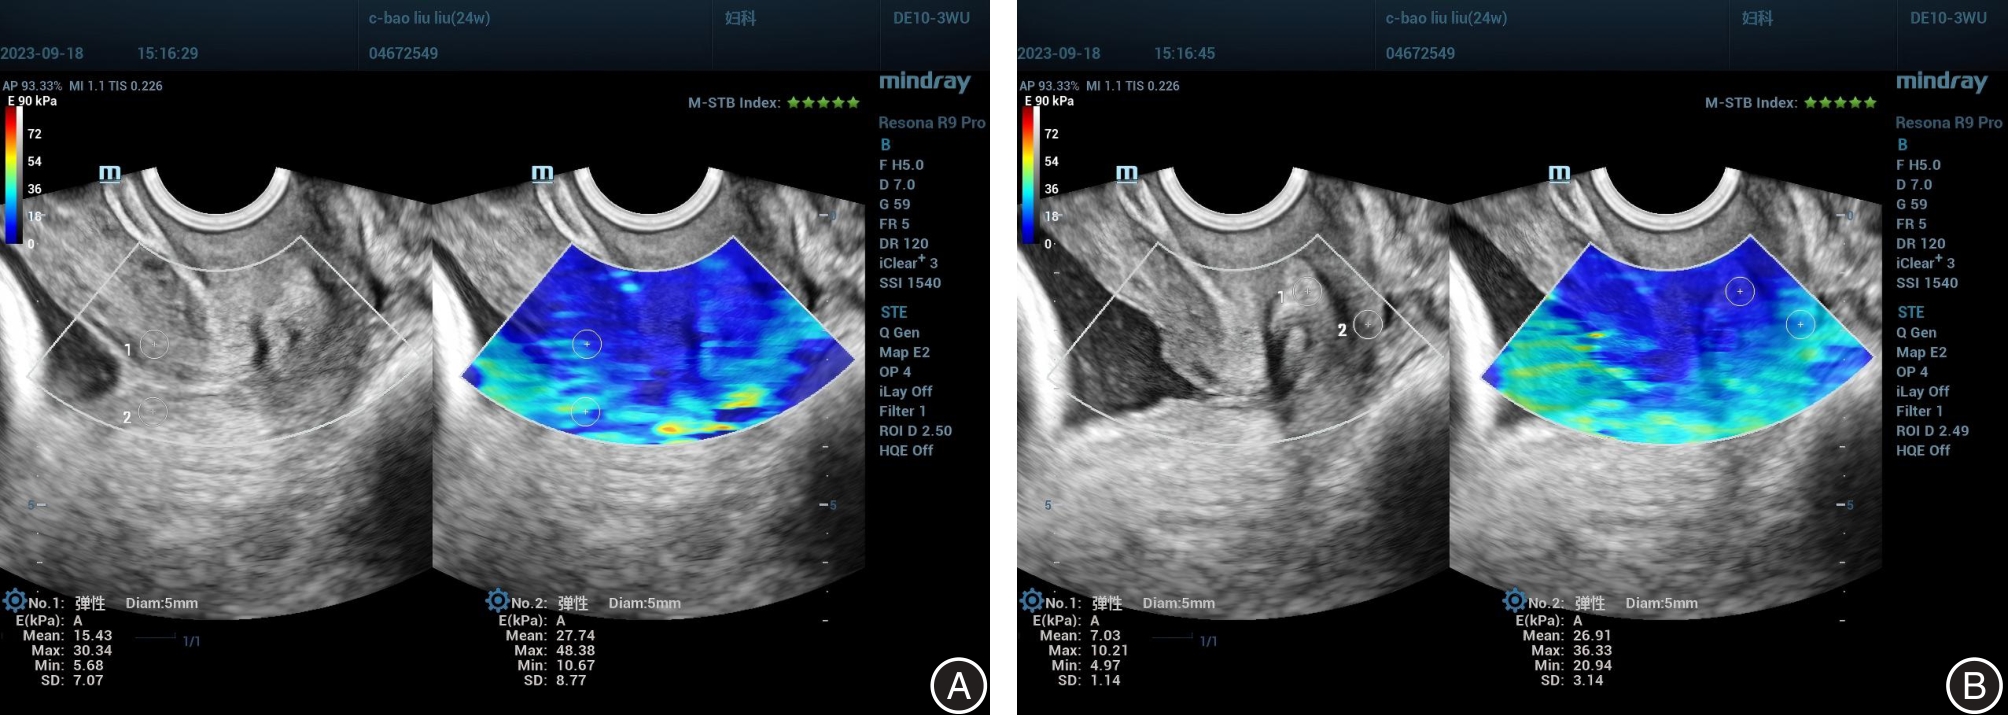

Minsui CAI,Qi CUI,Sujun DING,Xuejun. NI. Application value study of cervical shear wave elasticity imaging combined with cervical length and anterior cervical angle in assessing cervical function and predicting spontaneous preterm birth[J]. The Journal of Practical Medicine, 2025, 41(6): 896-903.